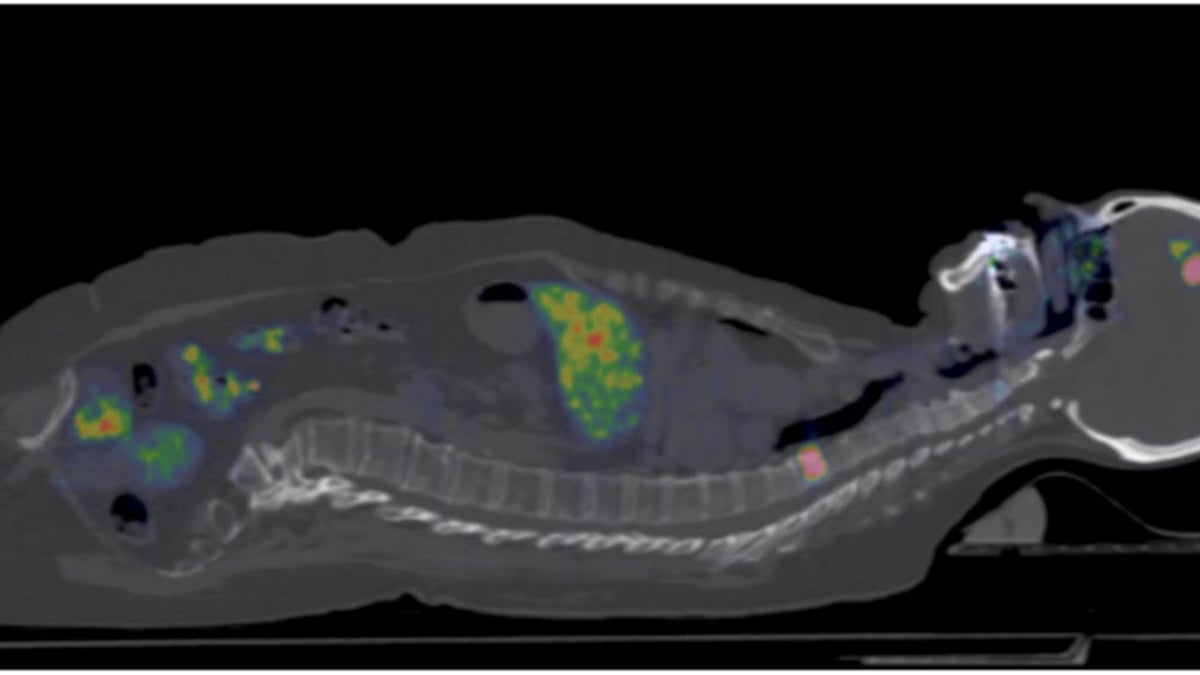

I september inleds en stor nordisk studie vars främsta mål är att med hjälp av pet-kamera se vilken typ av bröstcancer patienten har och därmed kunna anpassa behandlingen mer individuellt. Forskarna använder en metod som utvecklats vid Uppsala universitet och pet-centrum på Akademiska sjukhuset som gör det möjligt att upptäcka om kvinnan har så kallade HER2-positiva metastaser.

Den nya pet-metoden innebär att man använder ett litet protein/spårämne, en så kallad affibody, som kopplas till radioaktivt Gallium på pet-centrum vid Akademiska sjukhuset. Proteinet fungerar som målsökare och fäster vid HER2-proteinet. Proteinet sprutas in i ett blodkärl och transporteras vidare till resten av kroppen. När det fastnar i vävnader med mycket av HER2-protein kan pet-kameran läsa av radioaktiva signaler.

• Syftet är att med hjälp av ett radioaktivt märkt spårämne, affibody, och pet-kamera se om patienterna har HER2-positiva tumörer, vilket har stor betydelse för valet av behandling.

• Spårämnet som används är ett litet veckat protein kallat affibody, som utvecklats av Affibody AB i samarbete med forskare på Uppsala universitet och Akademiska sjukhuset. Proteinet fungerar som målsökare och fäster vid HER2-proteinet vilket signaleras till pet-kameran.

Effektivare diagnostik av bröstcancer utan biopsier är målet för en nordisk studie ledd från Akademiska. Forskarna använder pet-kamera och ett nytt spårämne.